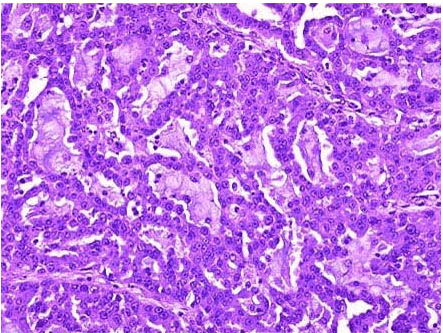

ACrohn病

B低分化腺癌

C中分化腺癌

D高分化腺癌

E黏液腺癌